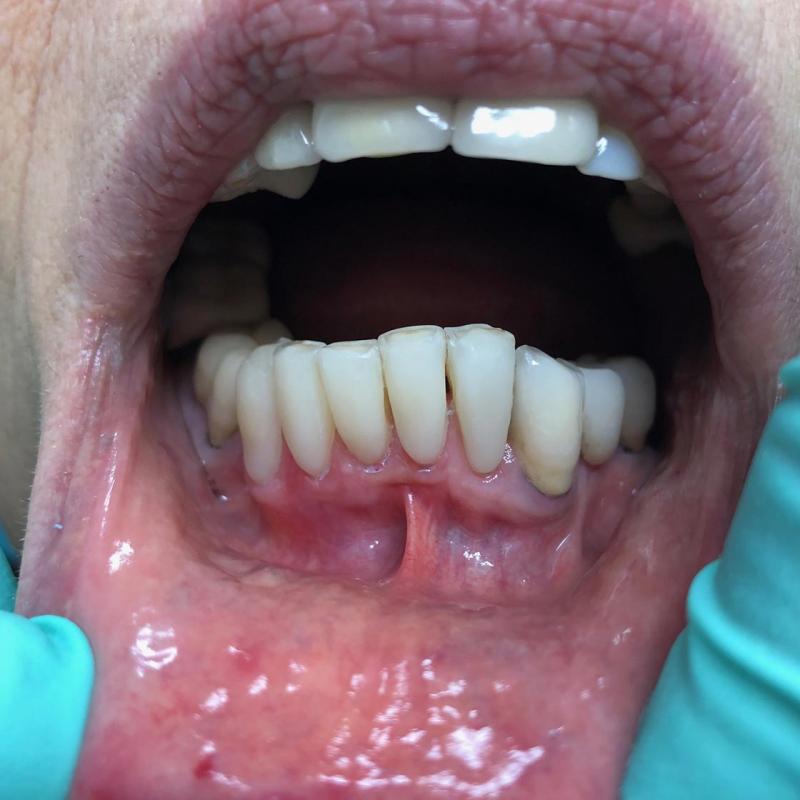

La parodontologia controlla il benessere delle strutture portanti dei denti (gengive e osso di sostegno) cercando di prevenire o curare la piorrea che nella popolazione adulta è la più frequente causa di perdita dei denti.

Oggi più che mai viene richiesta la copertura di esposizioni radicolari mediante la chirurgia estetica mucogengivale. Inoltre con la cura della piorrea si mantiene in buono stato la salute generale del paziente prevenendo complicanze cardiovascolari e diabetiche.